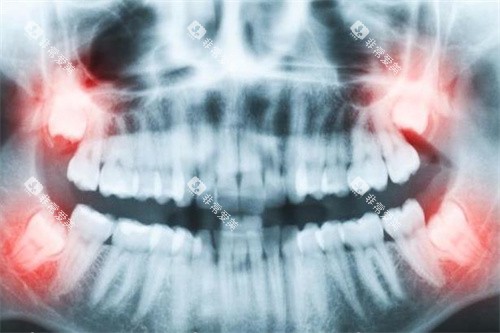

“同样是种一颗牙,为什么有的诊所报价3000,有的要1万?”在鹿寨做生意的李老板摸着下巴上的创可贴说,他上周刚在蓝天口腔做完半口种植。主刀医生梁瑞拿着他的CT片解释:“您选的韩国登腾种植体3000元起是基础价,但您牙槽骨萎缩需要加骨粉,这就多了2000元起;另外您要求用德国进口基台,比国产的贵1500元起。”

“比较坑人的是那些‘打包价’诊所,”梁院长翻着患者投诉记录说,“去年有位阿姨在别处花8000元起种牙,结果术后感染才发现用的竟是‘水货’种植体。”而在蓝天口腔,每颗种植体都有仅有溯源码,患者扫码就能查到生产批次和进口报关单。